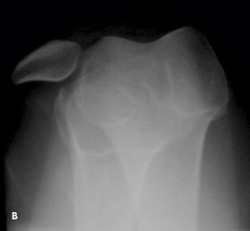

Knee pain following a soccer injury: The frontal radiograph reveals that the patella is dislocated laterally (A). This is confirmed on the sunrise radiograph (B). A lateral radiograph shows the malalignment of the patella with the distal femur (C). Most important, it also shows no fracture. Lateral dislocation of the patella is diagnosed.